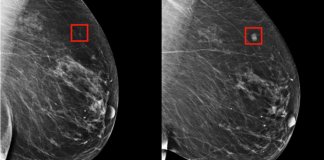

Com inteligência artificial, câncer de mama pode ser previsto cinco anos...

Eles desenvolveram um modelo para prever o câncer de mama até cinco anos antes de ele se manifestar. Mais um motivo para celebrar e incentivar o desenvolvimento científico e tecnológico.